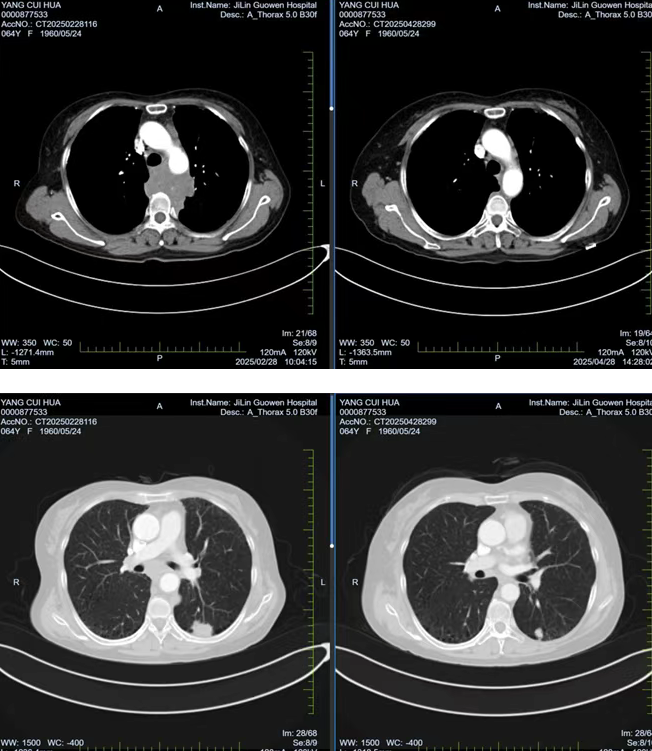

張阿姨因胸背部疼痛持續(xù) 1個月且逐漸加重,在當(dāng)?shù)蒯t(yī)院檢查時發(fā)現(xiàn)左肺存在腫物,初步考慮為惡性腫瘤。經(jīng)熟人介紹,了解到我院在腫瘤專科疾病治療方面的優(yōu)勢后,該患者前往我院就診。胸部腫瘤放化療二科為其安排了 PET/CT 檢查,并對左側(cè)鎖骨上腫大淋巴結(jié)進(jìn)行穿刺活檢,最終明確診斷為左肺下葉高級別神經(jīng)內(nèi)分泌癌,臨床分期為 cT1cN3M0 IIIb 期,且縱隔轉(zhuǎn)移淋巴結(jié)已侵犯椎體,患者因劇烈疼痛,生活質(zhì)量受到嚴(yán)重影響。

經(jīng)過 1 周期的免疫聯(lián)合化療后,患者的胸背部疼痛逐漸減輕,目前患者疼痛癥狀已得到改善,生活質(zhì)量得到了顯著提升。